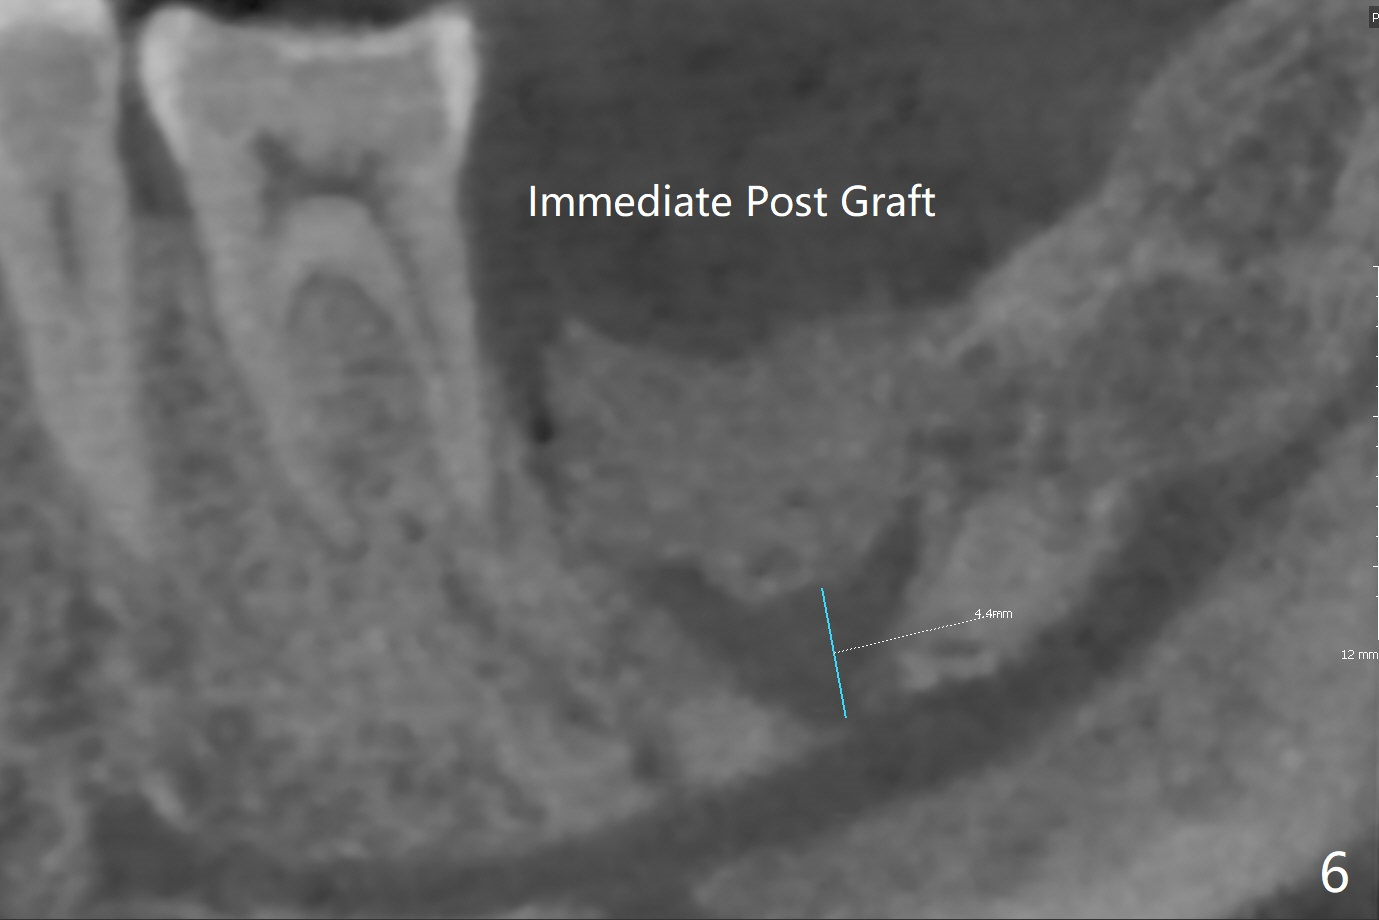

52岁男要求拔除松动左下7(图一,二),同意植骨,我们需要注意什么?我一般在类似情况下,使用浸润麻醉,但是今天改用block anesthesia,加浸润麻醉,直接将局麻药注射于牙龈,疼痛和出血控制好(图三:G(含有肾上腺素纱布)),麻醉方面有什么缺点?我不喜欢block anesthesia,万一碰到神经,麻醉深,病人不会给提醒。牙槽窝近中舌侧远中骨壁肉芽组织彻底清除;由于视野不好,切开(图四),牙槽窝底部*是软的,敢去除吗?其实我第一次向软组织投降,不敢去除,好像挺容易出血,接着敢植骨吗?其实植入粘性骨粉(皮质骨),术后CT检查表明遗留肉芽组织(图五:*),大约4毫米厚(图六),病人身体现在可忙乎了。覆盖PRF膜和不可吸收膜各一张,4-0 PTFE缝合,开口基本关闭,最后使用树脂敷料。